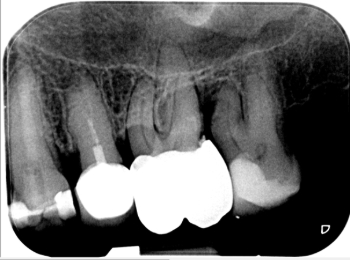

Röntgen Krone distal

25: apikal aufgehellt, Krone distal undicht, WF reicht nicht bis ins untere Drittel.

26 und 27 nicht erhaltungswürdig, vertikaler Knocheneinbruch.